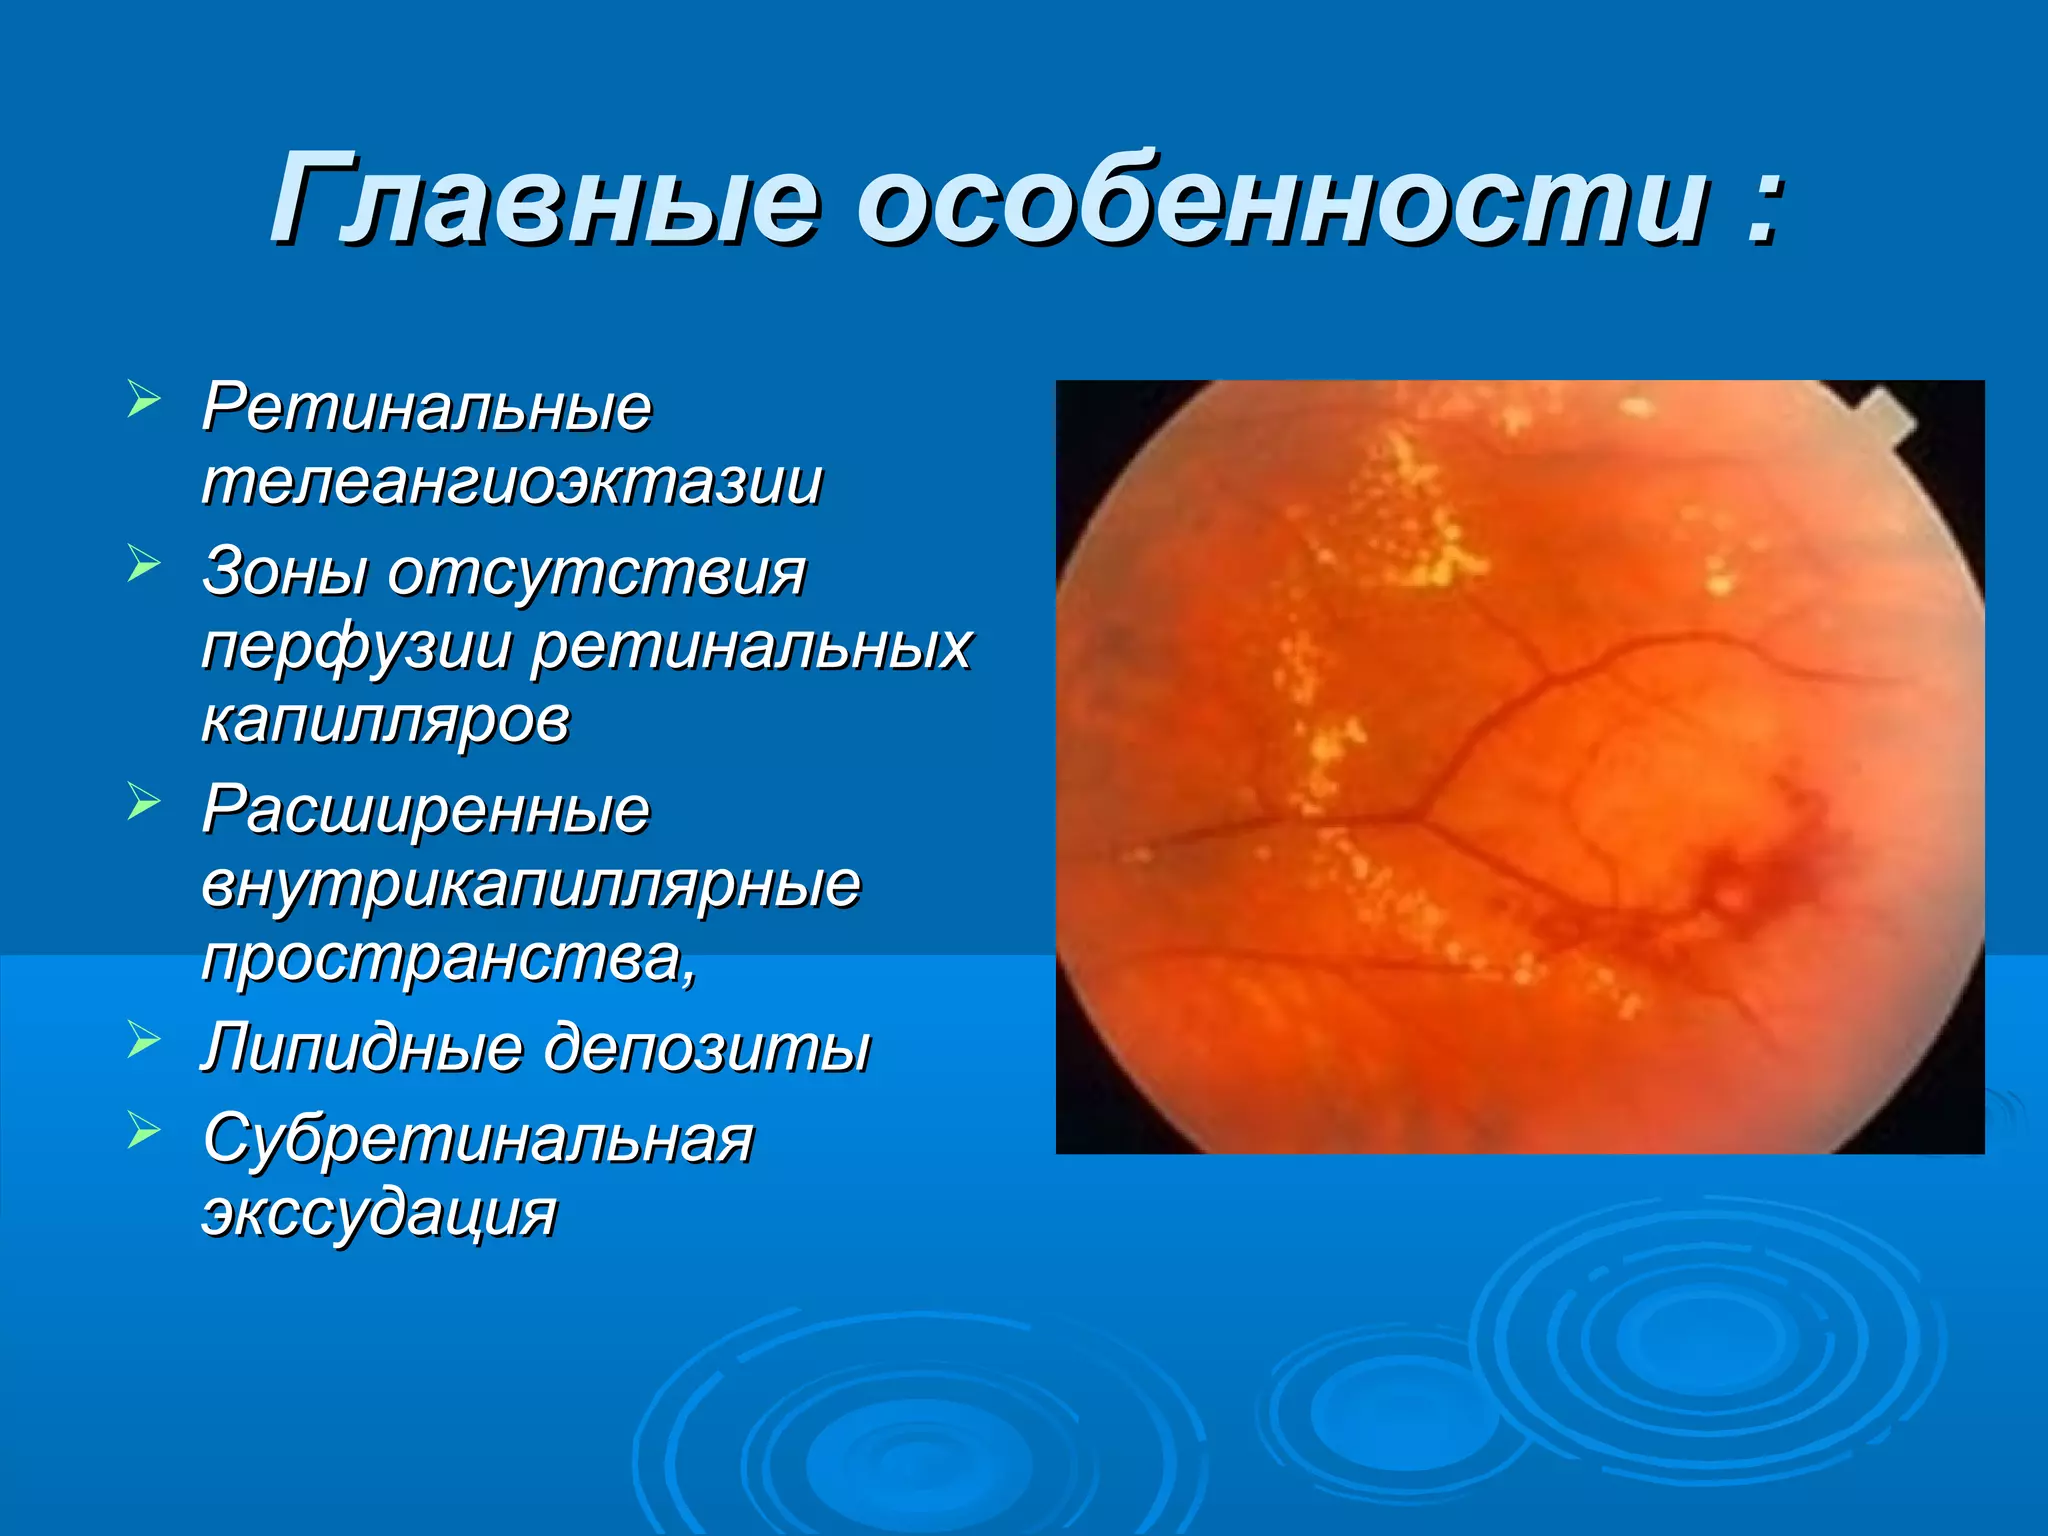

Болезнь Коатса - это идеопатическое заболевание, характеризующееся полиморфными изменениями сосудов сетчатки с массивной экссудацией, чаще всего у детей и подростков, с преобладанием среди мальчиков. Эпидемиология показывает, что заболевание проявляется, как правило, в возрасте 8-16 лет, но возможно его обнаружение и у взрослых. Основные проявления включают ретинальные аномалии, субретинальную экссудацию и постепенно прогрессирующую потерю зрения.